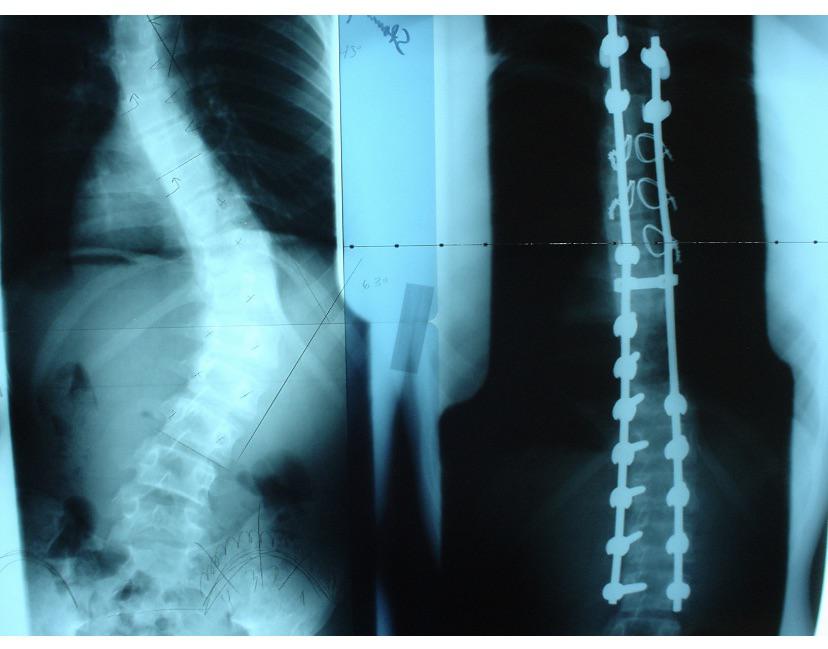

17. «Radiografía de mi espalda, antes y después de la cirugía de escoliosis (tomada en 2005).»

https://www.reddit.com/r/mildlyinteresting/comments/ccvdl2/xray_of_my_back_before_and_after_surgery_for/